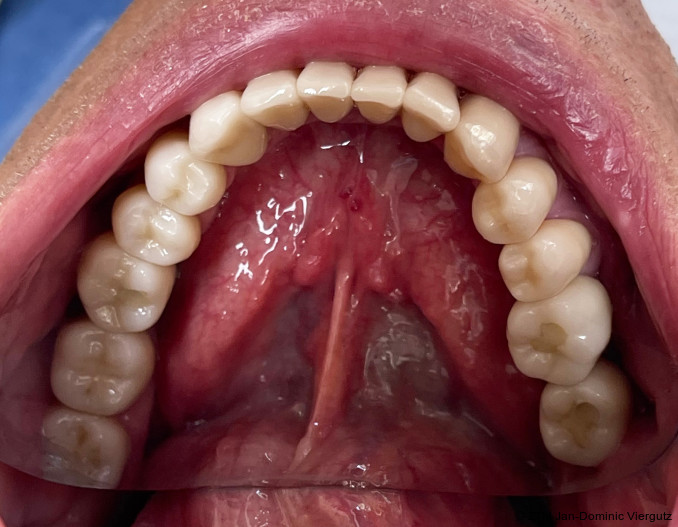

Der 58-jährige Patient stellte sich mit ausgeprägter Zahnarztangst und einem stark abrasiven Gebiss im Klinik am Schloss MVZ vor. Im Unterkiefer fehlten die Zähne 36, 37 und 46, was zu einer deutlichen Einschränkung der Kaufunktion führte. Klinisch zeigten sich starke Abrasionen an den vorhandenen Zähnen sowie Schmerzen im Bereich des Kiefergelenks. Zudem bestand ein wurzelbehandelter Zahn 11, der weiterhin Beschwerden verursachte. Im Bereich der fehlenden Zähne wurde ein Knochenrückgang diagnostiziert.